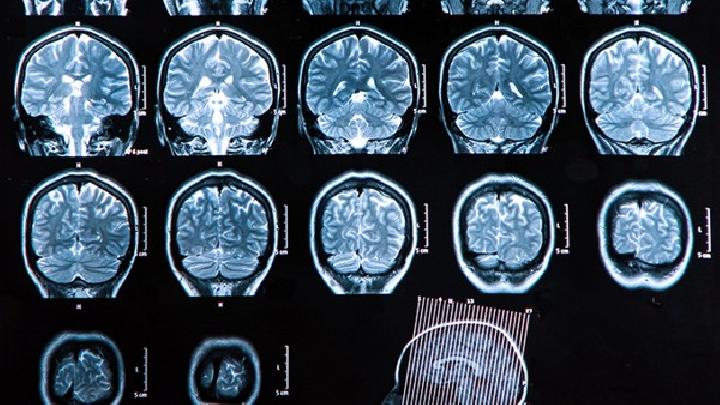

1.下丘脑综合征(HYPOTHALAMUS SYNDROME,HTS) 内分泌代谢功能障碍的临床特征,伴有自主神经功能障碍。其病因与临床表现有很大差异。临床症状和体征不能用单垂体或单靶腺体的损伤或其他原因来解释。因此,应结合具体症状和检查结果进行识别。